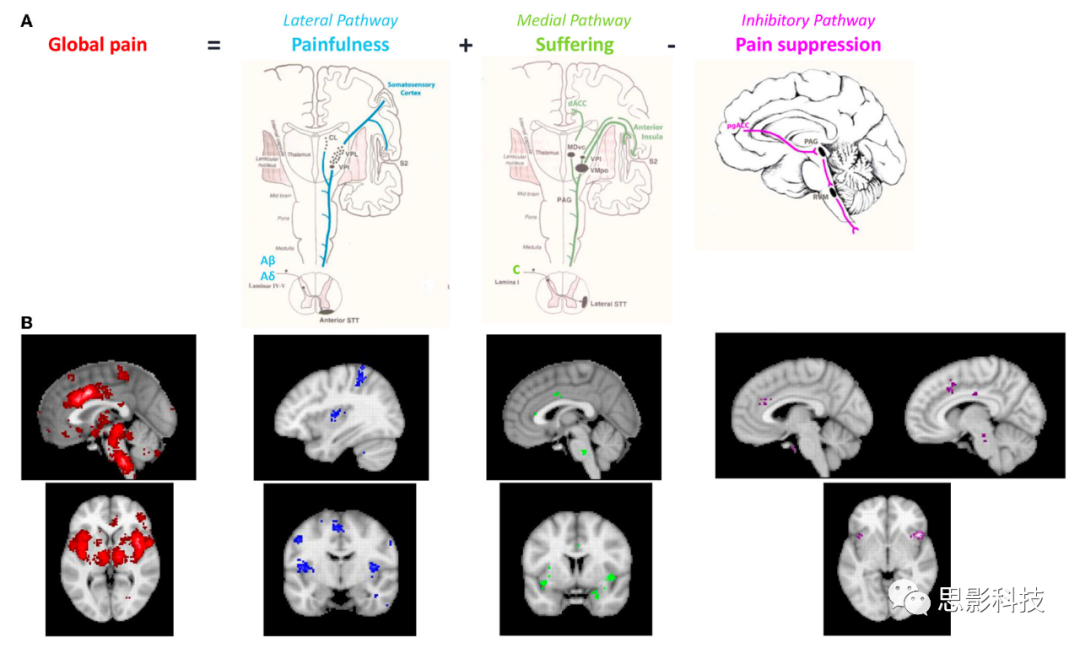

因此,从解剖学和症状学角度来看,慢性病理性疼痛可以分解为三个可分离但相互作用的通路,包括一个侧向的“疼痛感”通路,一个中央的“痛苦”通路,以及一个下行的疼痛抑制通路(25, 27, 28)(图2,图3)。尽管侧向体感和中央突显通路可以解释疼痛的疼痛感和情感成分,但尚未提出与慢性疼痛中遇到的慢性化和功能障碍相关的因素。我们建议将当前的疼痛网络扩展到三重网络模型以填补这一空白。

图 2. (A) 与疼痛的3个不同方面(疼痛感、痛苦和存在感)相关的解剖学通路。

(B) 对评估大脑中疼痛特征的不同组成部分的功能成像研究进行的Neurosynth元分析。疼痛的元分析(n = 516个研究,红色和蓝色),痛苦的元分析(n = 124,绿色)和抑制的元分析(n = 601,紫色)。这一图表和分析进一步强调了疼痛、痛苦和抑制在慢性疼痛中的不同角色和相互作用,以及它们在大脑中的神经生物学基础。这为更深入地理解疼痛的复杂性和多维性提供了有力的证据。

当个体报告说他们“疼痛”时,实际上涉及到三个组成部分,即他们有一定量的疼痛感,伴随着特定量的痛苦,持续特定的时间。这三个不同的统一疼痛感知组成部分可以与三个不同的疼痛处理通路相联系(图2)。

两个上行疼痛通路由解剖学和功能上可分离的中央和侧疼痛通路组成(28, 50-52)。中央疼痛通路,由前至rdACC和前岛叶皮层组成,处理疼痛的情感动机方面。因果关系由扣带体切除术干扰负面情感和认知控制的事实证明(53)。相关性分析进一步将rdACC与不愉快感联系起来(22, 28, 50, 52, 54)。侧疼痛通路,涉及体感皮层(SSC),编码疼痛的区分性/感觉成分,如疼痛感、疼痛定位和疼痛特性(灼热、疼痛等)(28, 51, 55)。第三条通路,即下行疼痛抑制通路,平衡两个上行疼痛通路(25, 26, 56, 57)。参与下行疼痛抑制通路的皮层区域包括前和pgACC、中脑导水管周围灰质、海马周围区域、下丘脑和腹内侧脑干(56-58)。下行疼痛抑制通路控制上下文依赖的疼痛感知(59)、安慰剂镇痛(58, 60-62),并在以全身性疼痛为特征的疼痛综合症中呈现不足(63)。因此,下行疼痛抑制通路反映了大脑抑制急性或持续疼痛的能力。一项关于脊髓电刺激的fMRI研究表明,疼痛抑制的程度取决于pgACC的激活程度,这是下行疼痛抑制系统的一部分(64)。

如果这些解剖学通路真正反映了疼痛的不同临床方面,那么应该能够通过功能成像,包括基于fMRI和EEG的成像来识别它们。基于516个fMRI成像研究的疼痛神经合成元分析(图2B,红色)显示了功能性BOLD激活与三个解剖学通路之间的很好的重叠,证实了这些解剖学区分的价值(29)。此外,对于不同的感觉方式,中央和下行通路可能是非特异性的或者在相邻的束中运行。实际上,124个功能成像研究的神经合成元分析发现,无论病因如何,痛苦都与dACC和前岛叶活动以及右侧缘上回有关(图2B,绿色)。根据601个研究的神经合成元分析,一般来说,抑制涉及突显网络,以及pgACC到rACC,以及后扣带皮层的前部分和右侧背外侧前额皮层,无论被抑制的刺激是什么(图2B,紫色)。这是一个侧化的网络,主要是右侧的。